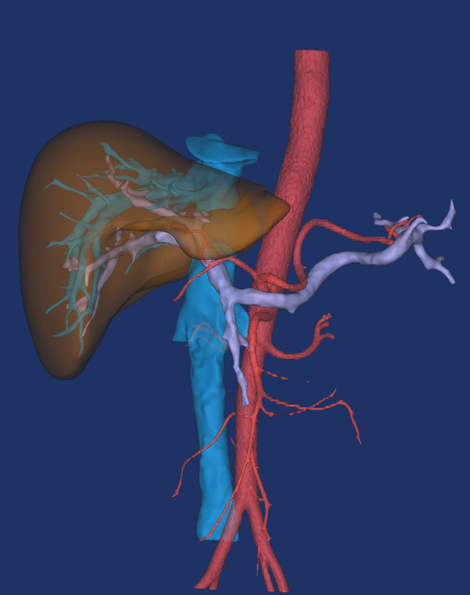

最后建模出来的效果:

正面图(肝脏+动脉+门静脉+腔静脉)                                反面图                                                          透视图